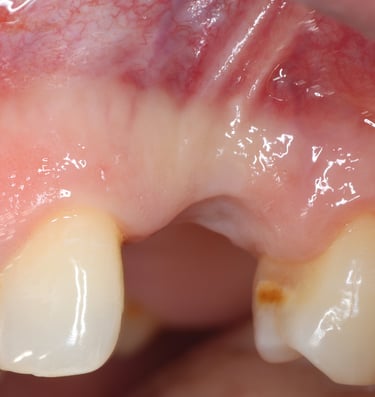

Chirurgie muco-gingivale

Traitement des récessions gingivales